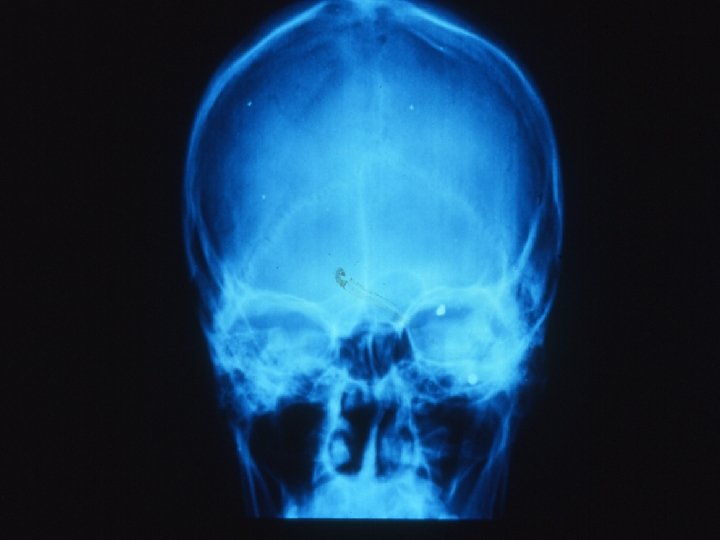

Traumatologie et Brûlures oculaires 3 -Contusion ouverte du globe oculaire Plaie perforante sans CE L’importance des lésions dépend de la taille de l’agent vulnérant, de sa trajectoire dans le globe, de la vitesse à laquelle il arrive sur l’œil Interrogatoire RX ou scanner au moindre doute de CE

Traumatologie et Brûlures oculaires 3 -Contusion ouverte du globe oculaire CEIO Le doute doit être constant Déterminer la nature du CE, sa trajectoire, risque de contamination( végétal, fer rouillé. . )

Traumatologie et Brûlures oculaires 3 -Contusion ouverte du globe oculaire SCANNER , RX standard dans toutes les positions du globe +/- écho. B Dés la moindre suspicion de CE